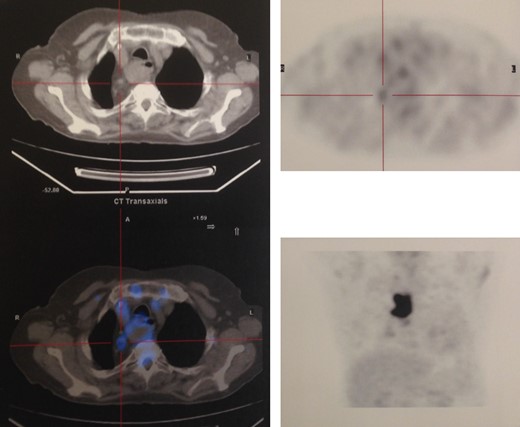

Staging with chest, abdomen and pelvic tomography, showed no signs of regional spread or metastatic disease (Fig. 2), and positron emission tomography scan revealed FDG (fluorodeoxyglucose) avidity in the primary lesion (retrosternal colic tube with thickened walls) and regional lymph nodes (Fig. 3).